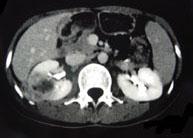

问题 女,33岁,右胁腹痛7天,尿检可见大量的脓细胞,CT平扫+增强如图所示,下列说法正确的是 ( )

选项 A、考虑为右肾囊肿合并感染 B、考虑为右肾脓肿 C、增强扫描可见该病灶不均匀强化,其内有无强化的坏死灶 D、右肾病灶边界模糊不清 E、右肾体积增大,其内可见类圆形低密度病灶

答案 BCDE